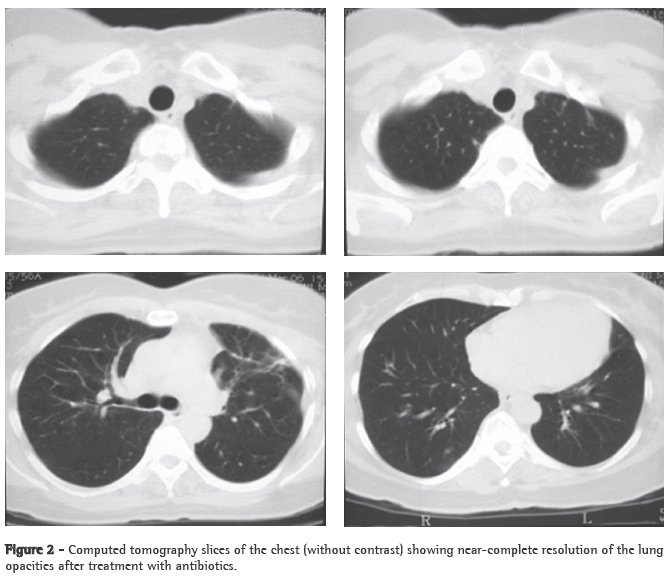

Abstract Lemierre's syndrome is characterized by acute oropharyngeal infection, complicated by internal jugular venous thrombosis secondary to septic thrombophlebitis, and by metastatic infections in various distant organs-most commonly in the lungs. We report a case of Lemierre's syndrome in a 56-year-old female who presented with right-sided neck mass and fever. Right internal jugular venous thrombosis was demonstrated on an ultrasound. A computed tomography scan of the chest revealed multiple opacities throughout both lungs. An open surgical biopsy was performed due to suspicion of pulmonary metastases. Anatomopathological examination revealed septic emboli in lung parenchyma. Retrospectively, the patient reported a history of pharyngitis two weeks prior to hospitalization. After the diagnosis had been made, the patient was treated with broad-spectrum antibiotics (cefuroxime for 7 days and azithromycin for 5 days; subsequently, because fever persisted, cefepime for 7 days). One month later, a computed tomography scan of the chest revealed resolution of the opacities.

A 56-year-old Caucasian female sought treatment in the emergency room presenting a painful, right-sided neck tumor for 5 days. The patient reported a dry cough and high fever for 3 days. She described herself as a nonsmoker. She was hypertensive and diabetic. She had experienced a myocardial infarction 3 years prior. At admission, the patient was dehydrated and afebrile (axillary temperature, 36.7°C). She presented normal respiration. Laboratory tests revealed increased erythrocyte sedimentation rate (92 mm). Ultrasound of the neck showed IJV thrombosis, and anticoagulation was started on post-admission day 4. A chest X-ray demonstrated at least two nodules in the left lung, one apparently cavitated and one with a diameter of 18 mm at its base, as well as an irregular lesion, 25 mm in diameter, in the right upper lung lobe. A transesophageal echocardiogram, performed in order to rule out endocarditis, demonstrated no vegetation. Due to the hypothesis of pneumonia, empirical treatment with oral cefuroxime (500 mg every 12 h) was started. A computed tomography scan of the chest revealed multiple bilateral lung opacities, with an aspect suggestive of metastatic implants (Figure 1). The patient was then submitted to fiberoptic bronchoscopy, the findings of which were normal. In the microbiological analysis of the bronchoalveolar lavage fluid, testing for acid-fast bacilli and fungi were negative, as were the cytopathologic study and cultures. Since the working diagnosis was metastatic neoplasm, the patient underwent surgical lung biopsy. The anatomopathological examination of the sample showed chronic suppurative inflammation with organizing abscesses in lung parenchyma. In view of the hypothesis of Lemierre's syndrome caused by jugular thrombosis accompanied by septic pulmonary embolism, the patient was questioned regarding the occurrence of tonsillitis at the onset of the disease. The patient had no recollection, but her daughter remembered that the patient had used oral amoxicillin (500 mg every 8 h for 10 days) for the treatment of tonsillitis some days prior to hospitalization. At hospital admission, the patient received a course of intravenous cefuroxime (750 mg every 8 h for 7 days) concomitantly with oral azithromycin (500 mg once a day for 5 days). Subsequently, because fever persisted, she was treated with cefepime (1,000 mg every 12 h for 7 days). A control computed tomography scan of the chest performed after this course of antibiotics showed nearly complete resolution of the opacities (Figure 2). The patient had been afebrile since the third day of the new course of antibiotics. No microorganisms were isolated from blood cultures or bronchoalveolar lavage cultures. Since there is no evidence that it is beneficial in cases of Lemierre's syndrome, anticoagulation was discontinued after 20 days.